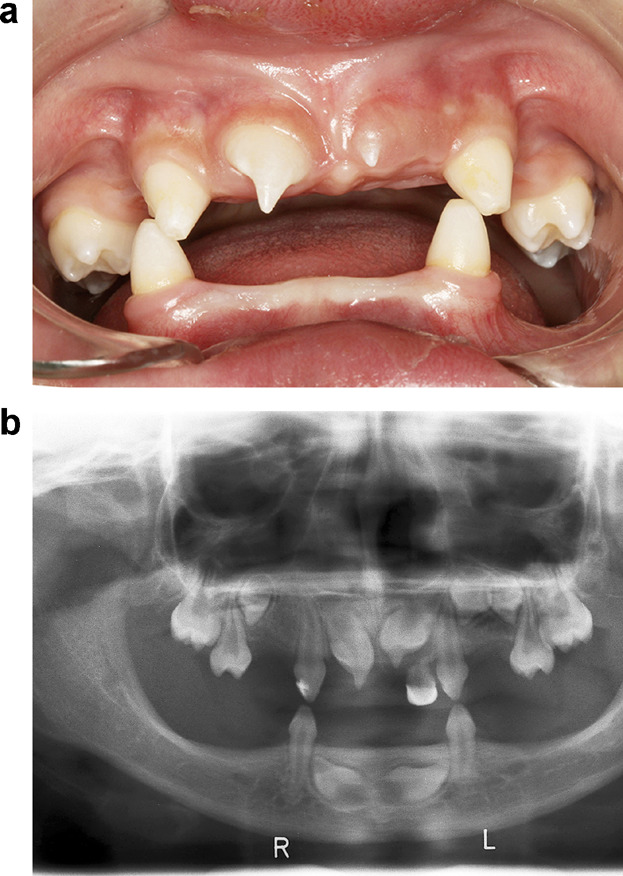

In terms of diagnosis, clinical features are important. Dentigerous cysts are usually discovered during routine dental exams or through radiographic evaluations. One of the key clinical features is that the cyst originates from the amelocemental junction, which is the junction between the enamel (the hard outer layer of the tooth) and the cementum (the specialized tissue covering the root of the tooth).

On an X-ray, the dentigerous cyst appears as a well-defined radiolucent area around the crown of the impacted tooth. It’s important to note that dentigerous cysts often don’t cause any symptoms and are found incidentally. However, if they grow in size or become infected, they can lead to swelling, pain, or displacement of nearby teeth.

As a dental student, it’s important to have a good understanding of dentigerous cysts. Dentigerous cysts are a type of cyst that form around unerupted or impacted teeth. They develop from a structure called the dental follicle, which surrounds the tooth germ or the developing tooth.